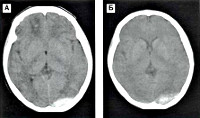

Эпидуральная и субдуральная гематома.

Описание

Средний объем эпидуральной гематомы составляет 120 миллилитров, минимальный — 30, максимальный — 250. Диаметр гематомы варьирует от 7 до 8 сантиметров. Обычно она локализуется в одной-двух долях мозга, чаще всего в височной области и смежных участках. Гематомы имеют утолщенную центральную часть, сужающуюся к периферии.

Компрессия твердой мозговой оболочки и вещества мозга происходит из-за несжимаемости гематомы, которая давит на оболочку, образуя вмятину. Основной причиной появления гематомы является повреждение средней оболочечной артерии и ее ветвей, реже — вен и синусов. В редких случаях источником кровотечения может быть диплое.